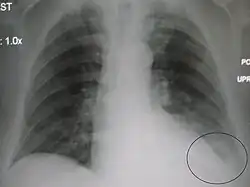

A black and white X-ray picture showing a triangle white area on the left side. A circle highlights the area.

A chest X-ray showing a very prominent wedge-shape bacterial pneumonia in the right lung